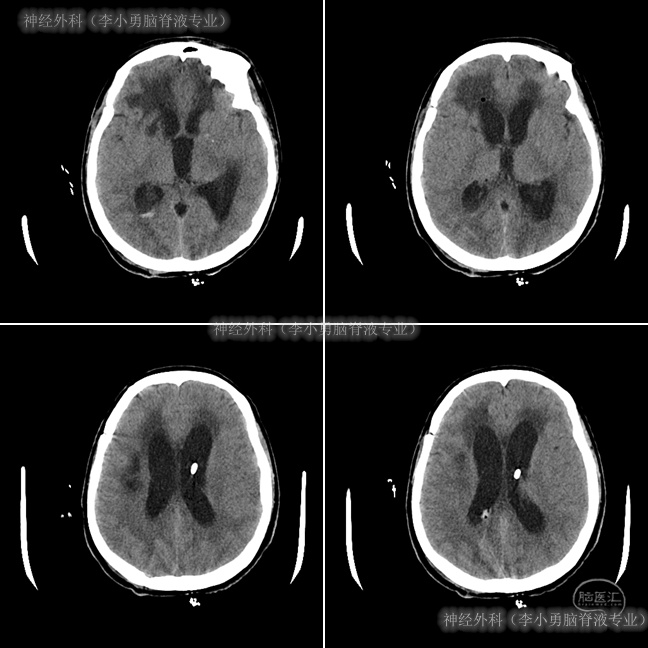

患者之后病情仍逐渐恶化,在2013年12月10日即分流术后8天(抗感染治疗6天后),再次出现昏睡,体温高达38.5 ℃左右,复查头颅CT示脑室扩张较术前没有变小或仍然较为严重的程度(图-7)。

图-7:分流术后8天头颅CT

患者体温逐渐恢复正常,但意识仍无明显改善,处于昏睡状态,于2013年12月13日即分流术后11天,查头颅CT(图-8)示脑室仍显著扩张。

图-8:分流术后11天头颅CT

考虑分流管压力过高,将“分流管泵”压力从2.0调至1.5,并腰穿测压为110mmH2O。调压后患者神志逐渐转清,能轻声言语、写字,但反应仍迟钝,于2013年12月24日即分流术后22天,查头颅CT示脑室较前有所减小,脑室周围水肿明显减轻(图-9)。根据此次头颅CT以及症状改善的结果,建议转院康复治疗。

图-9:分流术后22天头颅CT